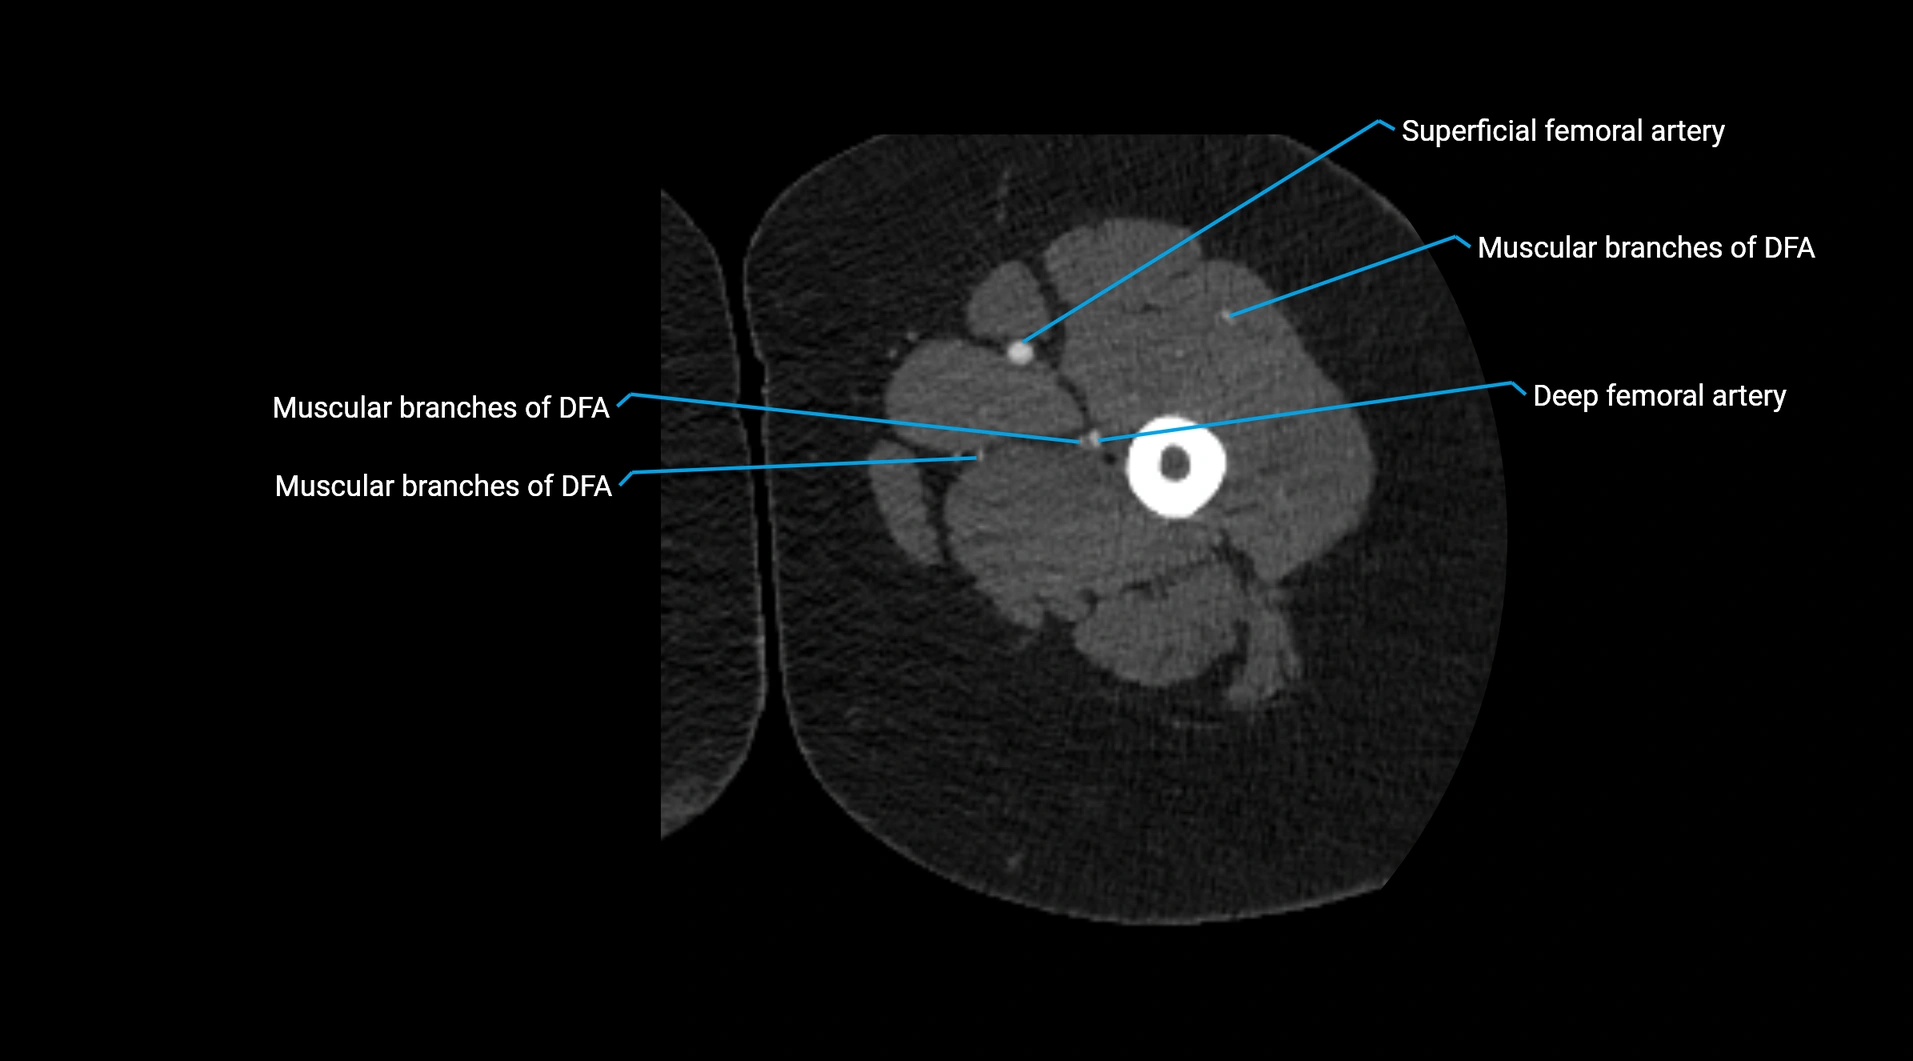

CT images

image

Contrast-enhanced CT (CTA):

• Gold standard for abdominal aortic imaging

• Provides excellent detail of lumen, wall, aneurysm, thrombus, and branch vessels

• Multiplanar and 3D reconstructions help in aneurysm measurement, stent graft planning, and dissection evaluation